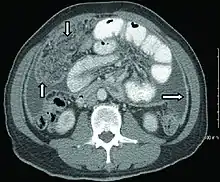

Gastrointestinal

Abdominal infections include gastrointestinal tuberculosis (which is important to distinguish from Crohn's disease, since immunosuppressive therapy used for the latter can lead to dissemination), tuberculous peritonitis, and genitourinary tuberculosis.[4]